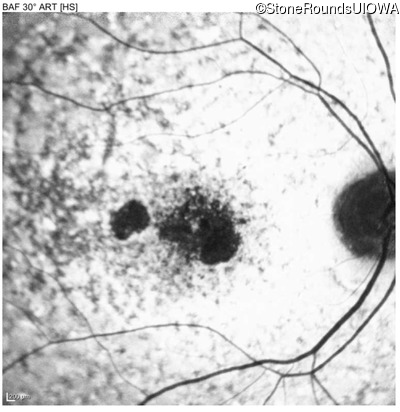

The clinical features favoring the diagnosis of ABCA4-associated autosomal recessive Stargardt disease in this patient include: loss of acuity at the beginning of the second decade, parafoveal photoreceptor loss on OCT, pisciform flecks in the macula with clear peripapillary sparing, and normally sighted parents.

All three of the cardinal ophthalmic features of Mendelian macular dystrophies are present in this patient. The most striking features of the fundus exam are the numerous yellow flecks at the level of the RPE. Flecks are most commonly seen in AR Stargardt disease and pattern dystrophy although they may be seen in some of the rarer Mendelian maculopathies as well. The visual acuity in patients with AR Stargardt disease is often "worse than the fundus looks" while the acuity in pattern dystrophy is often quite good despite extensive flecks. The pedigree of this patient is compatible with ABCA4-associated Stargardt disease and the better than expected acuity is attributable to foveal sparing (see below). The onset of reduced acuity at age 10 is much more characteristic of ABCA4 disease than pattern dystrophy. Another feature present in this patient that is very frequently seen in Stargardt disease is peripapillary sparing. However, this sign can be seen in pattern dystrophy as well. When central atrophy is present in ABCA4-associated Stargardt disease it often somewhat shiny (which is uncommon with the geographic atrophy of pattern dystrophy or age-related macular degeneration). Some patients with ABCA4-associated Stargardt disease can have some preservation of the fovea giving a zonal "bullseye" appearance to the center of the macula. Sometimes this preservation is associated with preserved acuity as in this case. The outer nuclear layer (ONL) is much thinner than normal on OCT, indicative of photoreceptor loss. This is associated with a thinning of the ellipsoid zone which is usually many times brighter and thicker than the external limiting membrane (ELM). These two lines are essentially equal in intensity in this patient. The foveal sparing is seen on OCT only as a small bit of retinal convexity in the center of the atrophy coupled with a small bit of residual RPE flanked by bare Bruch's membrane. The presence of a robust I2e isopter on Goldmann perimetry places this patient in the least severe half of all Stargardt patients (see Schindler, et al., 2010). Most patients with ABCA4-associated disease are somewhat myopic as is this patient. Stargardt patients also tend to perform very poorly on pseudoisochromatic plates, even when their acuity is still fairly good as it is here.